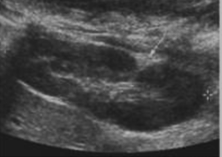

Nephrolithiasis (kidney stones)

Stones in the kidney. They are composed of calcium and salts. Kidneys are the second most common area for calculi in the body.

clinical indications for nephrolithiasis

Causes include metabolic disorders (calcium), high calcium intake, and chronic UTI’s. Common in Men >30 years old. Patients will present with acute back/flank pain that may radiate into the ipsilateral groin. Possible dysuria, hematuria, cloudy urine, fever, and/or chills.

Kidney stone image